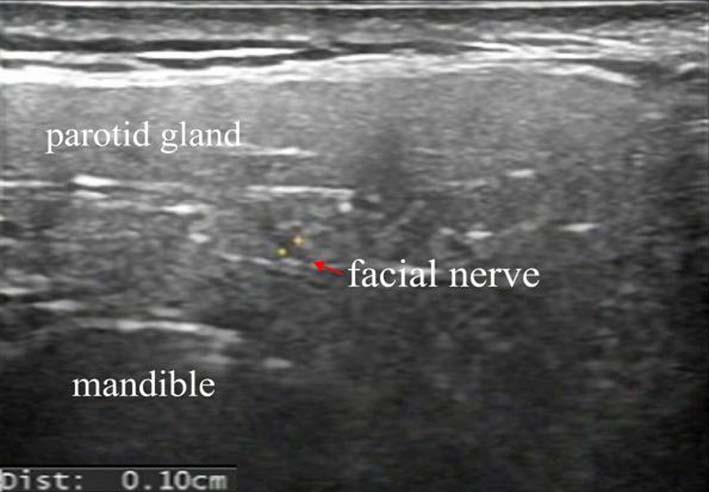

目的 通过高频超声(HFUS)探讨周围性面瘫(PFP)急性期患者颅外段面神经主干直径、局部血流动力学、面肌厚度的改变。 方法 纳入60例急性PFP患者作为PFP组,另纳入30例健康人群作为对照组。通过HFUS扫查并记录颅外段面神经主干直径(FN-d),面动脉直径(FA-d),面动脉收缩期流速(FA-Vs)、面动脉舒张期流速(FA-Vd)、面动脉阻力指数(FA-RI)、额肌厚度(FM-t)、降口角肌厚度(DAO-t)、降口唇肌厚度(DLI-t)等面部参数。评估各面部参数在PFP急性期诊断中的可行性,并进行组内及组间差异性比较,通过Pearson相关性分析PFP患者急性期面部参数与House-Brackmann(H-B)量表评分的相关性。 结果 (1)PFP组H-B量表评分显著低于对照组,差异有统计学意义(P < 0.05)。(2)不同检测者重复测量面部参数可信度良好(ICC > 0.75)。(3)PFP组患侧FN-d、FA-RI值高于健侧和对照组、FA-Vs、FA-Vd、DAO-t、DLI-t值低于健侧和对照组,差异有统计学意义(P < 0.05)。(4)PFP组患侧FN-d、FA-RI值与H-S量表评分成负相关(r = -0.847,P < 0.05;r = -0.863,P < 0.05);FA-Vs、FA-Vd、DAO-t、DLI-t与H-S量表评分成正相关(r = 0.808,P < 0.05;r = 0.757,P < 0.05;r = 0.836,P < 0.05;r = 0.694,P < 0.05)。 结论 HFUS可有效检出PFP患者急性期颅外段面神经主干直径的增加、局部微循环障碍以及面肌萎缩等特征性改变,且FN-d、FA-Vs、FA-Vd、FA-RI、DAO-t、DLI-t的增高与减低能够准确反映PFP的改善或进展,对临床病情监测和疗效评估具有重要的指导意义。

Objective To investigate the changes of diameter of the main trunk of the extracranial segment of the facial nerve, local hemodynamics and facial muscle thickness in patients with peripheral facial palsy (PFP) at acute stage by high frequency ultrasound(HFUS). Methods Sixty patients with acute PFP were enrolled as the PFP group, and 30 healthy people were selected as the control group.The following facial parameters were scanned and recorded using HFUS: diameter of the main trunk of the extracranial segment of the facial nerve (FN-d), facial artery diameter (FA-d), facial artery systolic velocity (FA-Vs), facial artery diastolic velocity (FA-Vd), facial artery resistance index (FA-RI), frontalis muscle thickness (FM-t), depressor anguli oris muscle thickness (DAO-t), and depressor labii inferioris muscle thickness (DLI-t).The feasibility of facial parameters in the diagnosis of acute-phase peripheral facial palsy (PFP) was evaluated, with intra-group and inter-group variability comparisons performed. Pearson correlation analysis was conducted to evaluate the relationship between acute-phase facial parameters and House-Brackmann (H-B) scale scores in PFP patients. Results (1)The H-B score of the PFP group was significantly lower than that of the control group, and the difference was statistically significant (P < 0.05). (2)The reliability of repeated measurements of facial parameters by different testers is good (ICC > 0.75). (3)The FN-d and FA-RI values on the affected side of PFP group were higher than those on the healthy side and control group, and FA-Vs, FA-Vd, DAO-t and DLI-t values were lower than those on the healthy side and control group, with statistical significance (P < 0.05). (4)The FN-d and FA-RI values of the affected side in the PFP group were negatively correlated with the H-S scale score (r = -0.847, P < 0.05; r = -0.863, P < 0.05); FA Vs, FA Vd, DAO-t, DLI-t are positively correlated with H-S scale scores (r = 0.808, P < 0.05; r = 0.757, P < 0.05; r = 0.836, P < 0.05; r = 0.694, P < 0.05). Conclusions HFUS can effectively detect the characteristic changes such as the increase in the diameter of the extrcranial facial nerve trunk, local microcirculation disturbance and facial muscle atrophy in patients with PFP in the acute stage, and the increase and decrease of FN-d, FA Vs, FA Vd, FA-RI, DAO-t, and DLI-t can accurately reflect the improvement or progress of PFP, which has important guiding significance for clinical disease monitoring and efficacy evaluation.